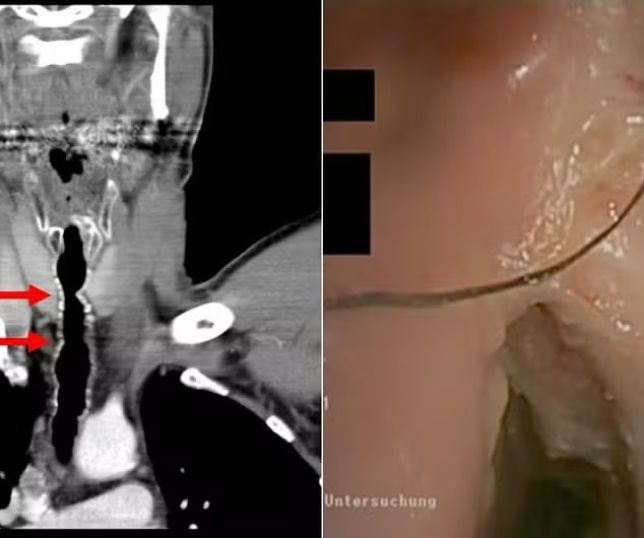

O caso dela foi descrito no American Journal of Case Reports em 21 de junho. A condição é conhecida como fetus in fetu (FIF) ou gêmeo parasita. No caso da menina, o feto tinha cerca de 18 centímetros e tinha desenvolvido até braços, cabelos e olhos.

A anomalia é rara e consiste no desenvolvimento de um resquício de embrião ou feto dentro do corpo do irmão gêmeo, com a junção dos corpos de forma semelhante à de gêmeos siameses, mas com a total assimilação do corpo de um pelo outro. Isso geralmente ocorre no abdômen da criança. Apenas cerca de 20 casos são conhecidos por terem ocorrido dentro do crânio.

Em uma ressonância, os médicos viram a cápsula que as defesas do corpo da menina tinha feito ao redor do feto e pensaram se tratar de um tumor de grandes proporções. Exames mais detalhados, porém, apontaram a presença de ossos, indicando que se tratava de um feto mal-formado.

Como ele estava comprimindo o cérebro da bebê, levando à uma hipertensão craniana, foi feita uma cirurgia para retirada do feto. Este é o único tratamento possível para casos de FIF. Os médicos descobriram que além do gêmeo parasita, vários tumores se desenvolveram ao redor de onde estava o feto.